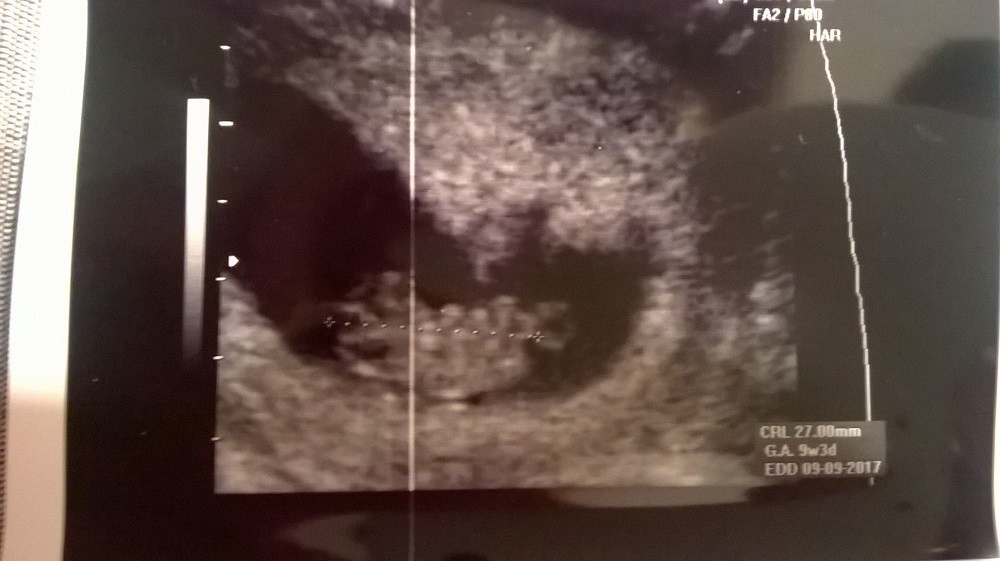

10 tc wedle OM

9 tc wedle usg

Zobacz załącznik 794679

Zobacz załącznik 794680